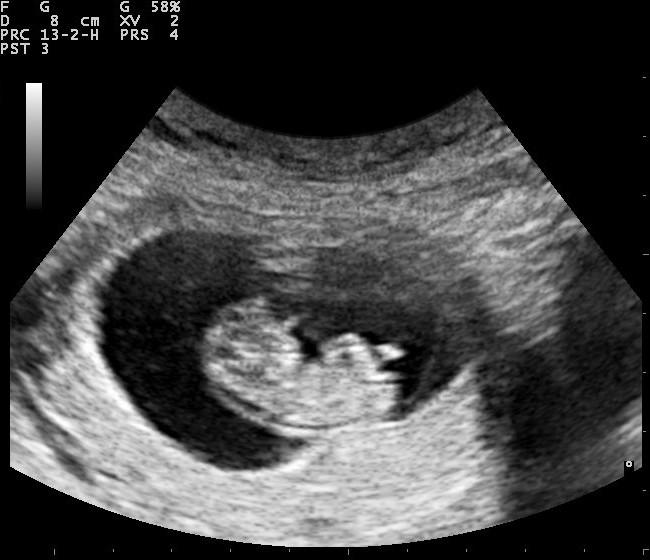

Снимка: Nevit Dilmen/Wikimedia Commons

2754 двойки за подали заявления в Центъра за асистирана репродукция /ЦАР/. Това показва докладът на ЦАР за първите шест месеца на 2024 г. В посочения период Центърът е сключил договори за дейности по асистирана репродукция с 25 лечебни заведения. По данни на клиниките, традиционно най-голям брой пациентки има във възрастовата група от 30 до 35 г., следвани от групата 36-39 г.

Броят на клиничните бременности през първото полугодие е 883. Това представлява 34,60 процента от преминалите пациентки. Броят на ражданията е 555, а броят на родените деца при двойки, финансирани от Центъра, е 651. Двуплодните и триплодни бременности са 108.